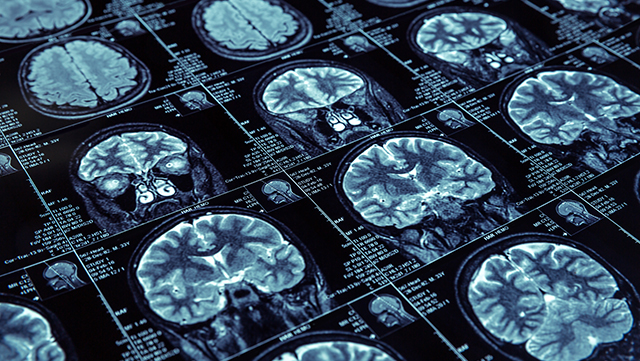

While there is no treatment to stop the progression of a heart-wrenching disease like Alzheimer's, let alone a cure, University of Alberta researchers are working at the forefront to solve the puzzle.

Unraveling the Alzheimer's enigma can't happen soon enough, as the disease that robs people of their memory and personality affects an estimated 47,000 Albertans today. That number is expected to nearly double over the next 15 years when one in five Albertans will be a senior.

Sue-Ann Mok, assistant professor in biochemistry, is one of the U of A scientists at the Neuroscience and Mental Health Research Institute using a blend of biochemical, cell biology and genetic approaches to pull apart the Alzheimer's mystery.